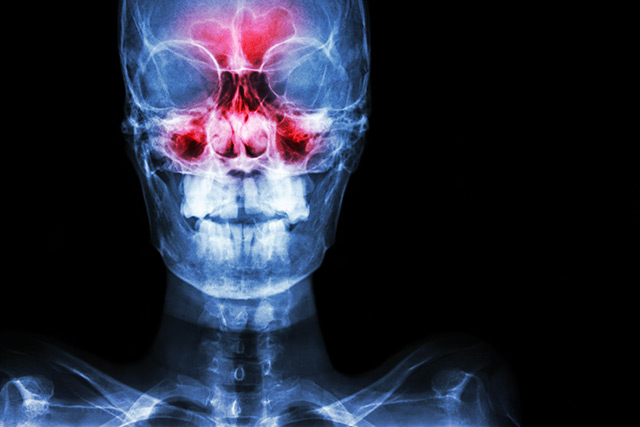

The experience is universally wretched. A building pressure in the forehead, a nose that runs incessantly and a general malaise that clouds the day. This is sinusitis, an inflammation of the sinus cavities often triggered by infections or allergies. For most, these infections are acute, resolving within seven to ten days. Yet the interim can feel interminable, marked by a constant, dull headache with swelling around the nose, eyes and cheeks. The discomfort can radiate to the scalp, ears and jaw, even making the teeth ache. Simple acts like bending over or moving quickly exacerbate the throbbing pressure, while the senses of smell and taste diminish.

"Sinusitis is an inflammation of the sinus cavities surrounding the nasal passages," said BrightU.AI's Enoch. "It is often triggered by factors like colds, allergies or dental infections, which lead to mucus accumulation. This mucus then creates an environment where bacteria and other pathogens can thrive."